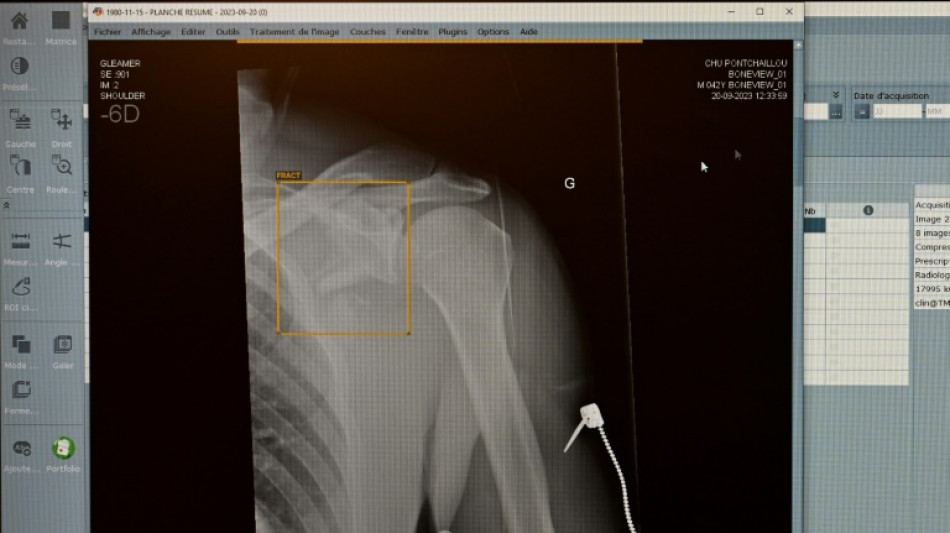

TÜV-Verband: Weniger Röntgengeräte mit Mängeln - Risiken bleiben aber / Foto: © AFP/Archiv